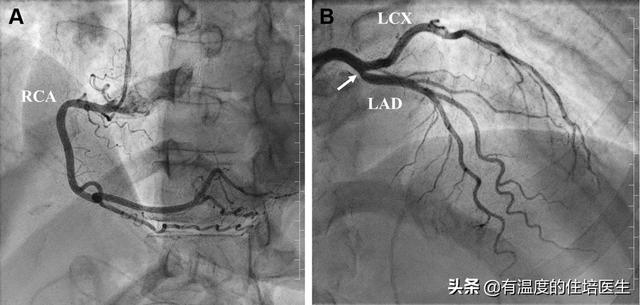

5.冠動脈造影

- 冠動脈造影は検査のために入院が必要で、侵襲的である。

- 冠動脈診断の現在のゴールドスタンダードである、はっきり見えるという利点があり、ある検査で閉塞が非常に深刻であることが判明すれば、再手術の必要なく直接ステントを入れることができる。

でも、その後だ。超音波検査、冠動脈CT、そして特に冠動脈造影検査が行われるようになってから、冠動脈疾患の診断は本当に問題ではなくなりましたこれには、心臓のどの血管がどの程度閉塞しているかを正確に把握することも含まれる。

チューブを心臓に通して選択的に撮影することで、血管を見たいところを見ることができ、血管がどの程度詰まっているかもわかります。

したがって、冠動脈造影は冠動脈疾患の診断のためのゴールドスタンダードであり、冠動脈CTはスクリーニング検査に過ぎないことを忘れてはならない。

6.冠動脈造影冠動脈造影は侵襲的な検査であり、現在でも冠動脈疾患診断の "ゴールドスタンダード "である。.狭窄病変の位置を特定し,その範囲を推定することができる。内腔径が70~75%以上縮小すると血液供給に重大な影響を及ぼすことが一般に認められている。

3、冠動脈造影:もし冠動脈CTAが冠動脈性心臓病の診断の銀の標準であるならば、冠動脈造影を金の標準と呼び、誰の意見もあってはならない、冠動脈性心臓病の診断を確認する最も正確な検査であり、誰もない。

まず、最も信頼できる検査は心臓冠動脈造影検査で、心臓のどの血管が詰まっているか、どの程度詰まっているかなどを明確に知ることができる。

1、冠動脈造影

これは冠動脈疾患を判定するためのゴールドスタンダードであり、冠動脈疾患の診断を確定し、その程度を明らかにするために用いられる。利点は、冠動脈が開いているか、プラークや狭窄があるかどうかを医師が目視で観察できることです。また、状況に応じて、適時にステント治療を行うことができます。